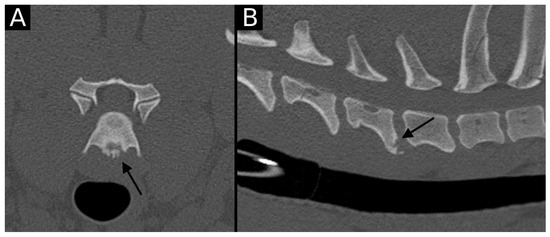

The junction between the endplates and intervertebral discs of the cervicothoracic junction (C6–C7, C7–T1 and T1–T2) were evaluated for the presence of alterations. When present, they were also graded and scored for EPJA, IVD herniation, spondylosis deformans, endplate sclerosis, articular process joint osteoarthrosis, and the presence of vertebral morphological abnormalities. The scoring system for endplate junction alterations and other spinal abnormalities was based on the proposed scoring by Tellegen et al. [13] for presumed EPJF at the lumbosacral spine. Endplate junction alterations were classified into four types (A, B, C, D): Type A involved presence of irregularity of the endplate margins without an obvious free fragment (Figure 1 and Figure 2); Type B involved avulsion evidenced by a thin rim of bone associated with a defect in the dorsal edge of the adjacent endplate (Figure 3); Type C included frank avulsion of a bony fragment (Figure 4) and Type D included presence of bony avulsion of both endplates. If EPJA was present, location (dorsal or ventral) and lateralization of the defect were also recorded. IVD herniation was graded from grades 0 to 3: grade 0 indicated no to mild (0–24%) herniation; grade 1 indicated mild to moderate (25–49%) herniation; grade 2 indicated moderate to marked (50–74%) herniation; grade 3 indicated marked herniation to complete obliteration (75–100%) of the vertebral canal by disc material. Spondylosis deformans was scored from grades 0 to 3: grade 0 indicated no enthesophytes; grade 1 indicated a small enthesophyte at the edge of the epiphysis that does not extend past the endplate; grade 2 indicated the presence of an enthesophyte that extends beyond the endplate but does not connect to the adjacent vertebra; and grade 3 indicated connecting enthesophytes from adjacent vertebrae forming a mineralized bridge. The other mentioned abnormalities (IVD mineralization, endplate sclerosis and articular process joint osteoarthrosis) were scored as present (1) or absent (0).

Figure 3. Transverse (A) and sagittal (B) reconstructions in bone algorithm. Contour irregularities lined by mild sclerosis are observed at the dorsal aspect of the T1 cranial endplate. A small, non-displaced mineral structure is observed at the same level (arrow). This is consistent with EPJA Type B.